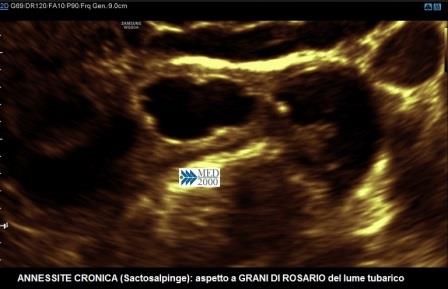

Un segno caratteristico di questa fase è la presenza di piccoli noduli iperecogeni (2-3 mm.) della parete interna che conferiscono un aspetto a "grani di rosario"; questo aspetto è legato alle pliche endosalpingee che in questa fase sono appiattite e interessate da una intensa fibrosi.